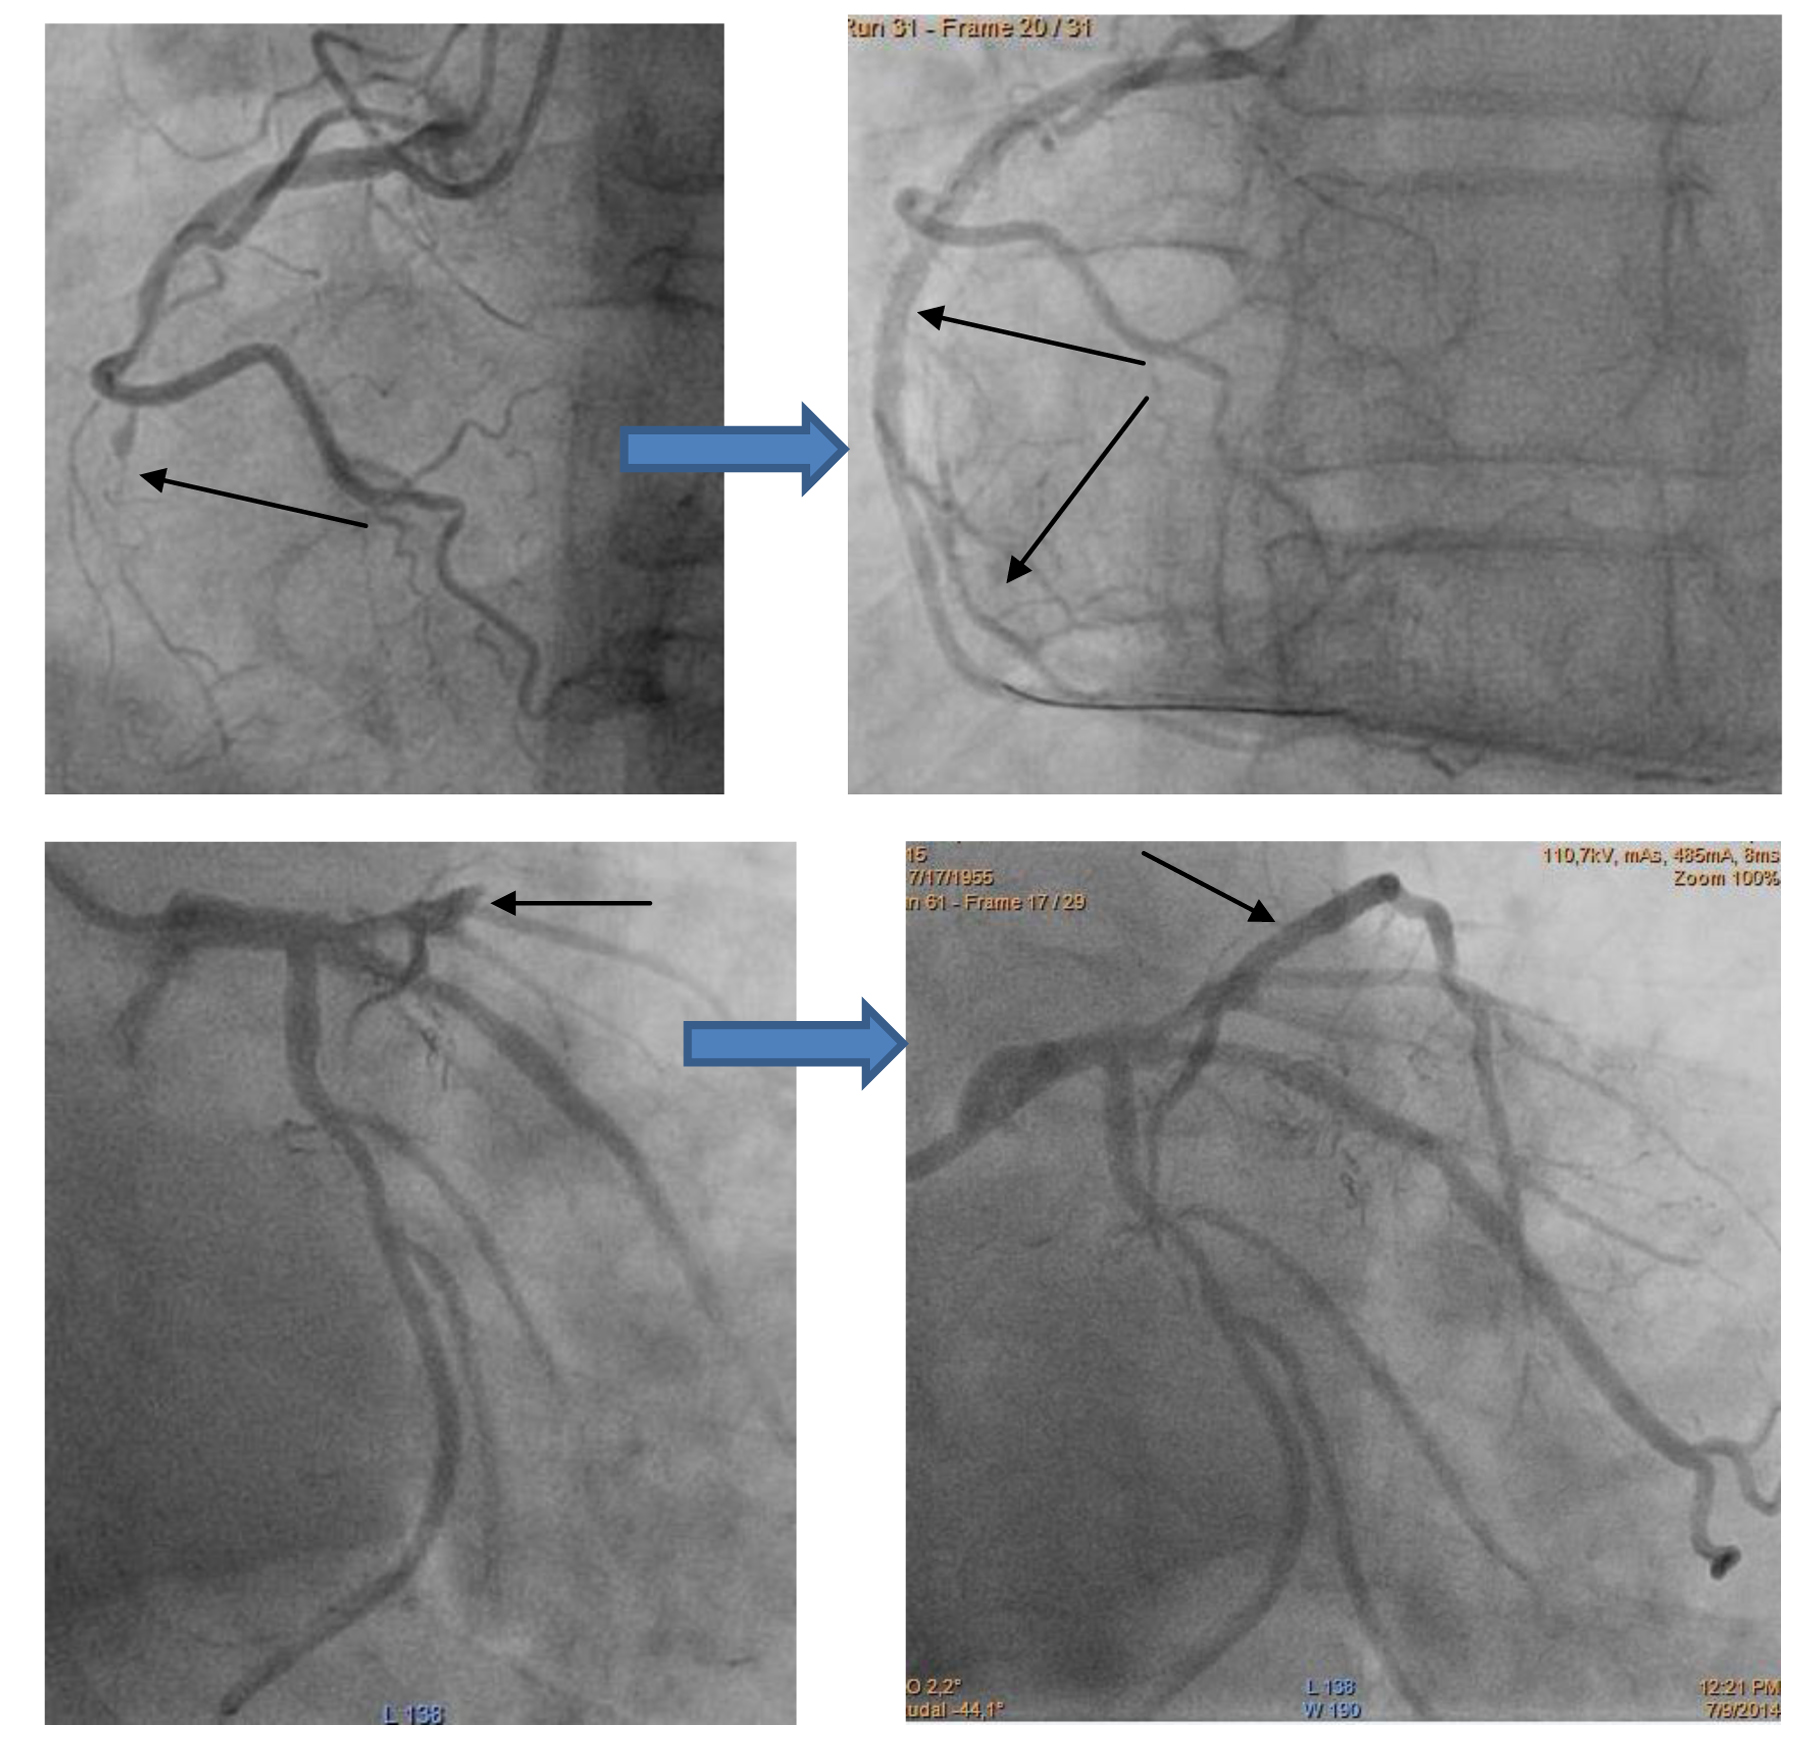

3. Лечение пациентов с поражением ствола левой коронарной артерии (ЛКА).

Также является одной из наиболее сложных тем в интервенционной кардиологии. Ствол ЛКА – довольно ответственный участок коронарного дерева для любого пациента. Это анатомическая зона отхождения сразу двух артерий сердца. Соответственно ствол ЛКА обеспечивает питание не менее 2/3 сердечной мышцы. Любые вмешательства с вовлечением ствола ЛКА требуют повышенной осторожности и сопровождаются высоким риском. Поэтому пациенты с поражениями ствола часто отправляются на открытую хирургическую операцию – аортокоронарное шунтирование (АКШ). Однако стентирование ствола ЛКА, тем не менее, в последнее время выполняется в мире всё чаще. Доказано, что при выполнении стентирования специалистами, имеющими большой опыт выполнения таких вмешательств, при использовании современных стентов с лекарственным покрытием результаты подобных вмешательств не уступают результатам АКШ, при этом избавляют пациента от необходимости вмешательства под наркозом на открытом сердце. В нашей клинике такие вмешательства также успешно выполняются. Ниже приводится 2 примера: а) стентирование с вовлечением ствола ЛКА одним стентом; б) стентирование с вовлечением ствола ЛКА двумя стентами. Самочувствие обоих пациентов с ишемической болезнью сердца в результате выполненного вмешательства значительно улучшилось, не требует повторных операций в динамике за период наблюдения. Стентирование в обоих случаях выполнено лучевым доступом.